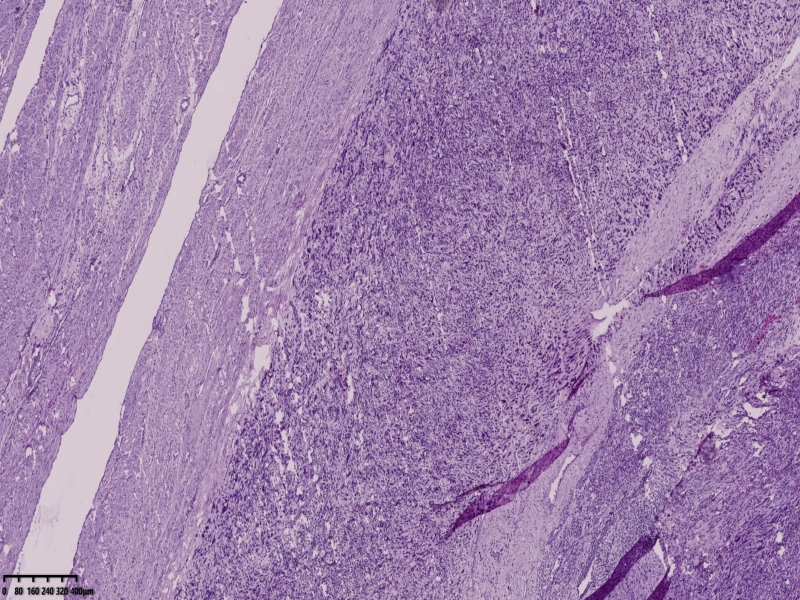

送检全子宫,宫体已被临床切开,内膜光滑,厚约0.1厘米,肌壁厚约2厘米,肌间可见肿物,已被临床切开,直径约8厘米,切面灰白灰黄。诊断软,局部质地脆。大体印象子宫平滑肌肉瘤待除外。

镜下可见肌间可见梭形瘤细胞,细胞核畸形,多核瘤巨细胞。坏死。